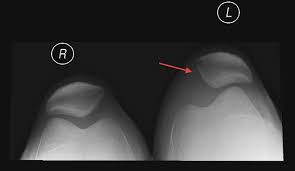

Η επιγονατίδα κινείται πάνω και κάτω από το κέντρο του γονάτου σε ένα αυλάκι (την τροχιλία) στο μπροστινό μέρος του μηρού. Η σταθεροποίηση της επιγονατίδας στην αυλάκωση γίνεται κυρίως από οστεοδείς παράγοντες (το βάθος και την μορφολογία του αυλακιού). Υπάρχουν επίσης σύνδεσμοι που ενισχύουν την σταθερότητα της επιγονατίδας μέσα στην αυλάκωση. Αυτοί οι συνδέσμοι βρίσκονται σε κάθε πλευρά του γόνατος και εμποδίζουν την επιγονατίδα να κινείται έξω από την τροχιλία. Αυτοί είναι ο έσω επιγονατίδο-μηριαίος σύνδεσμος (MPFL) και ο έξω επιγονατίδο-μηριαίος σύνδεσμος (LPFL).

Υπάρχουν ασθενείς στους οποίους η επιγονατίδα έχει την προδιάθεση να μετατοπίζεται έξω από την τροχιλία αναπτύσσοντας μια κατάσταση που ονομάζεται “εξάρθρωση”. Προδιαθεσικοί παράγοντες για την εξάρθρωση της επιγονατίδας είναι:

1. η ρηχή τροχιλία,